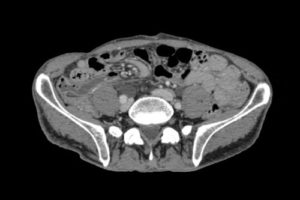

Для комплексной оценки распространенности патологического процесса часто проводят процедуру КТ почек и брюшной полости, которая показывает взаимные отношения структур данной анатомической области, состояние сосудов и лимфатической системы.

Зачем делают КТ ангиографию почек

КТ-обследование сосудов почек проводится для выявления патологий почечных артерий, вен, а также онкологические процессы, которые оказывают влияние на кровеносные сосуды. Ангиография позволяет выявлять аномалии развития артерий почек, стенозы, вазоренальные конфликты, артерио-венозные мальформации, степень сдавления сосудов прорастающими опухолями.

Диагностика проводится с контрастным усилением, поскольку без введения препарата такое сканирование будет недостаточно информативным.